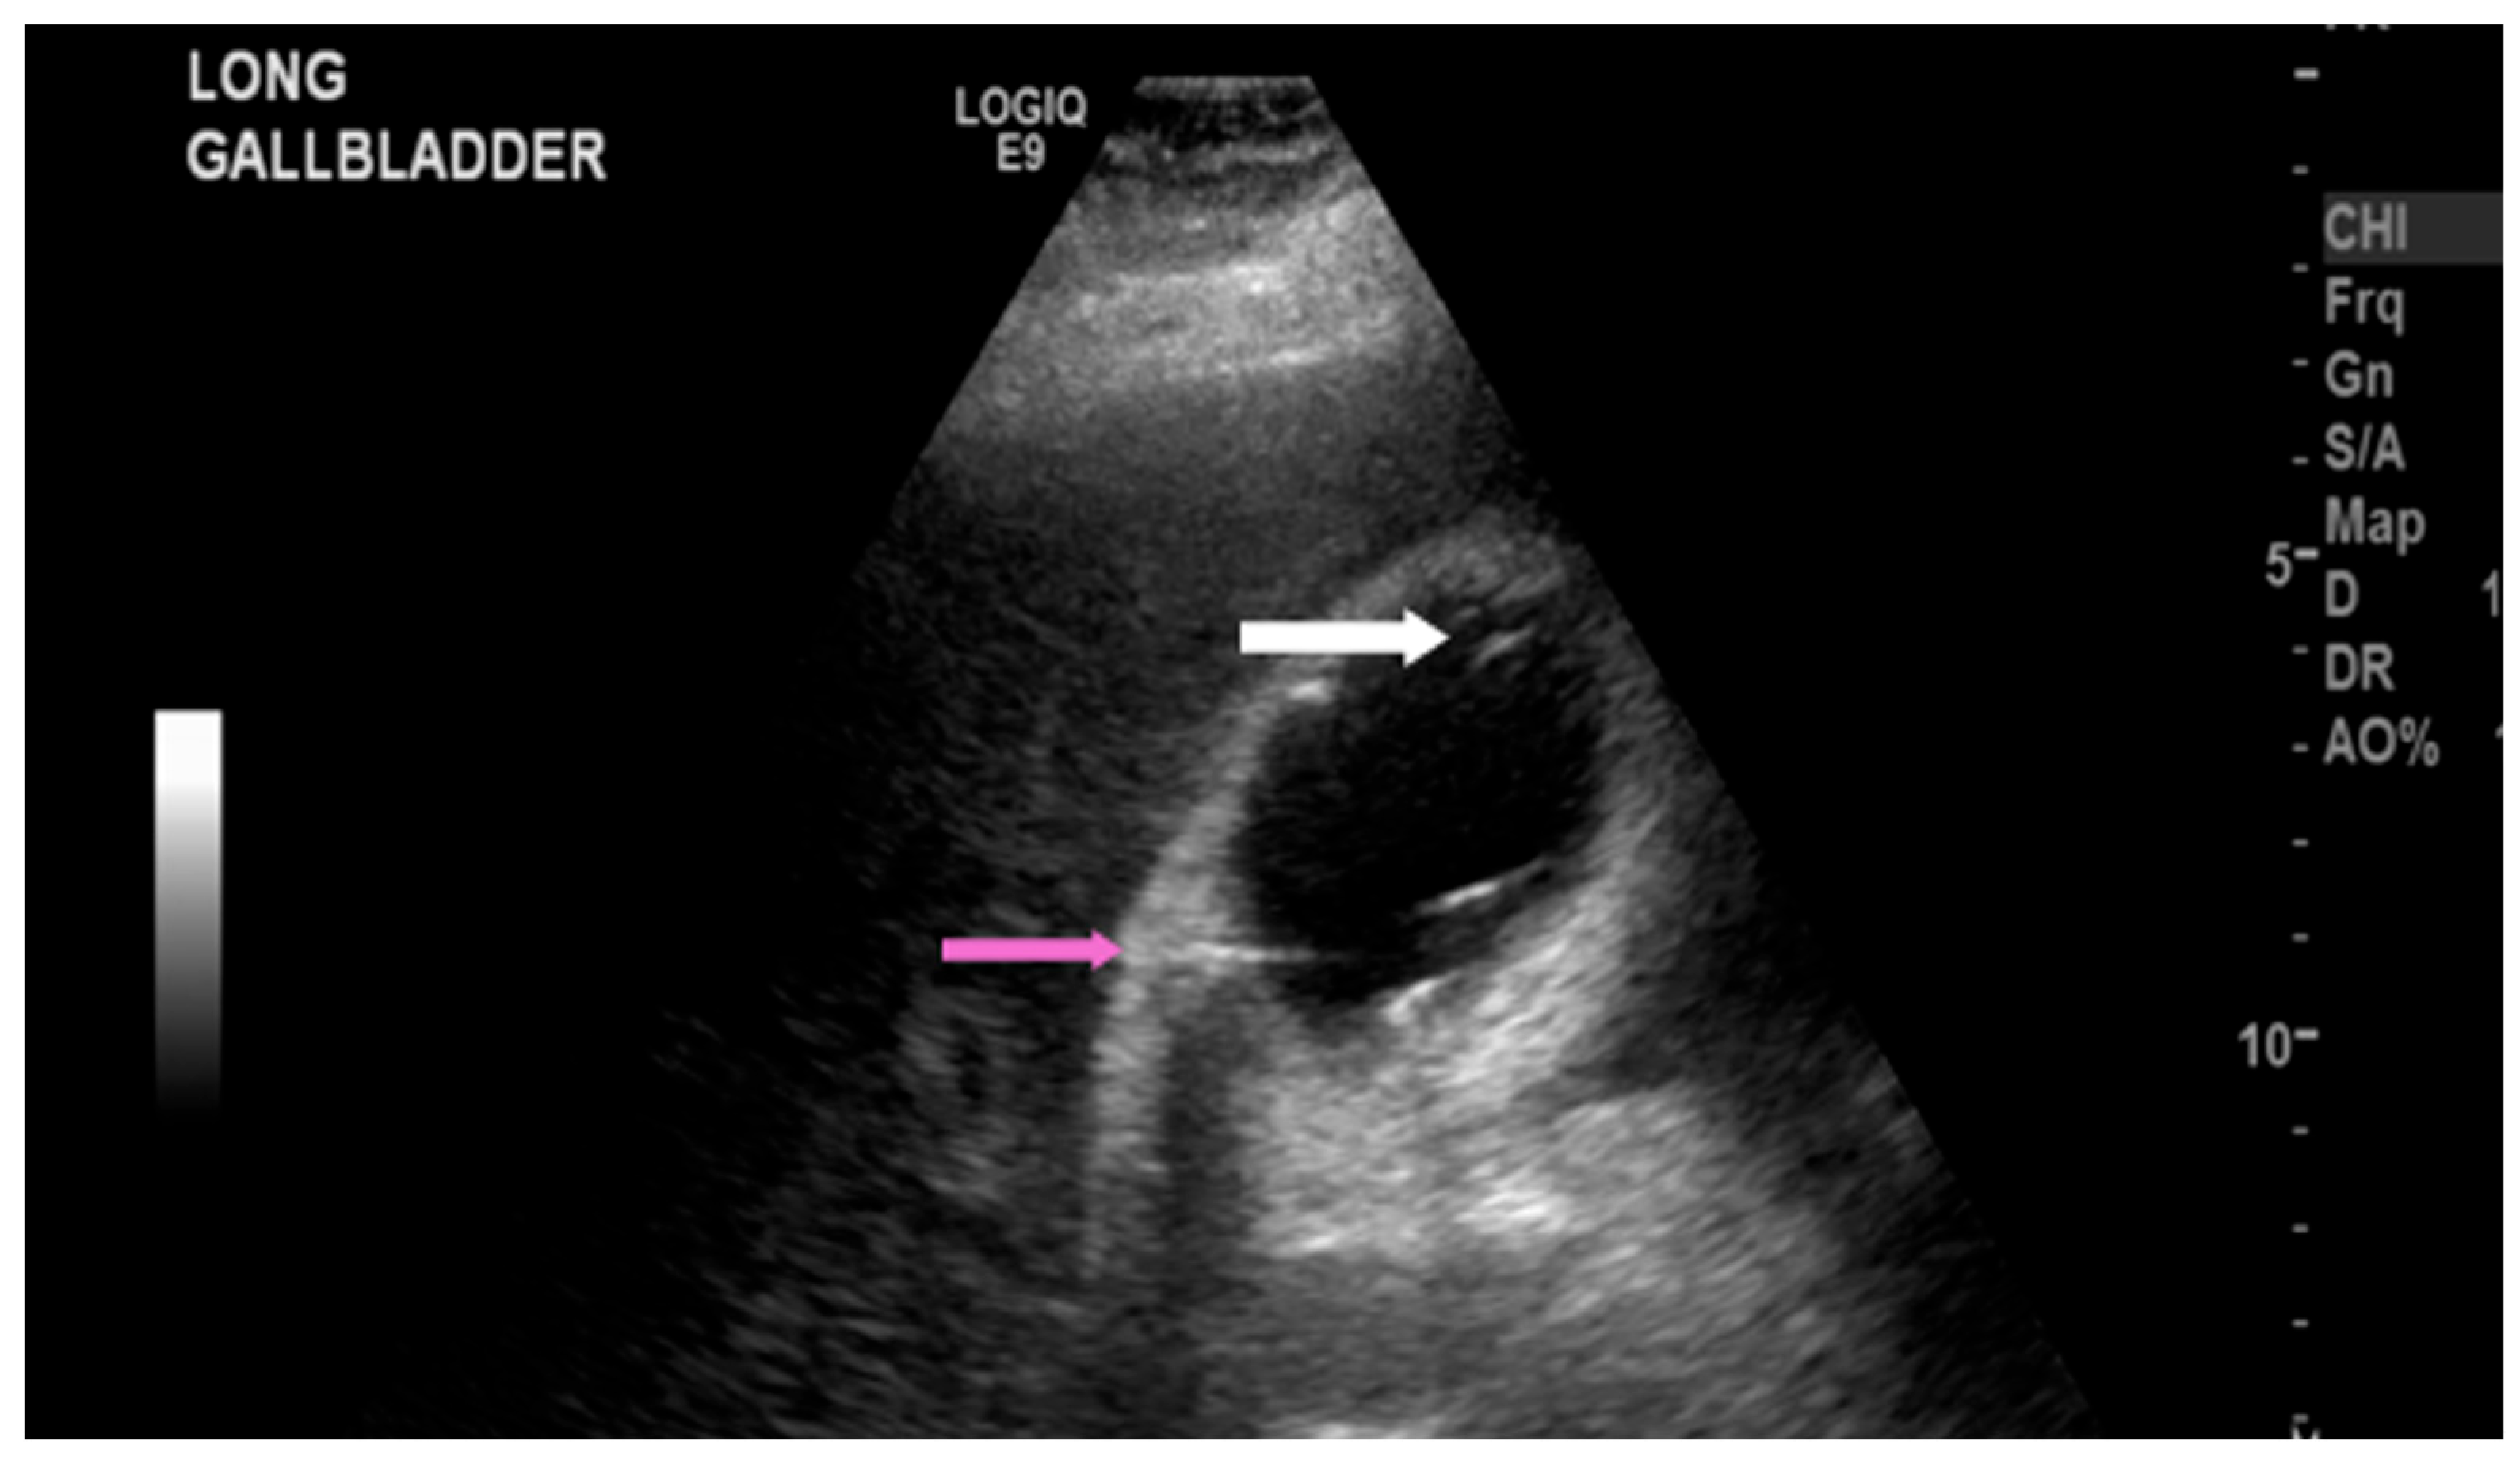

The most common sonographic finding of EC is the presence of gas within the gallbladder wall or lumen, which appears as highly echogenic foci accompanied by posterior dirty shadowing or reverberation artifacts, such as ring-down artifact, shown in Figure 1 and Figure 2. These artifacts are due to reflection and scattering of ultrasound waves by intraluminal gas. When the hyperechoic foci layer in the non-dependent portion of the gallbladder is present with low-level posterior shadowing, the appearance has been termed “the champagne sign” [16]. Furthermore, with changes in patient positioning, the gas may demonstrate mobility or layering on decubitus or upright imaging, aiding EC diagnosis. However, potential mimics of the visualized gas include gas secondary to recent instrumentation, biliary–enteric anastomoses, or sphincterotomy, which are important to consider clinically.

Figure 2. Right upper quadrant ultrasound of a 52-year-old female human immunodeficiency virus patient with emphysematous cholecystitis. Foci of air in the gallbladder lumen (white arrow) and intramural air (pink arrow) were demonstrated.